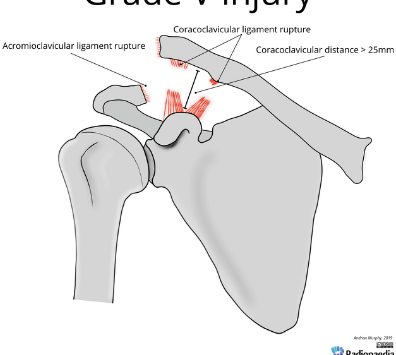

Based off Rockwood classification of acromioclavicular joint injury, what grade would this be?

5